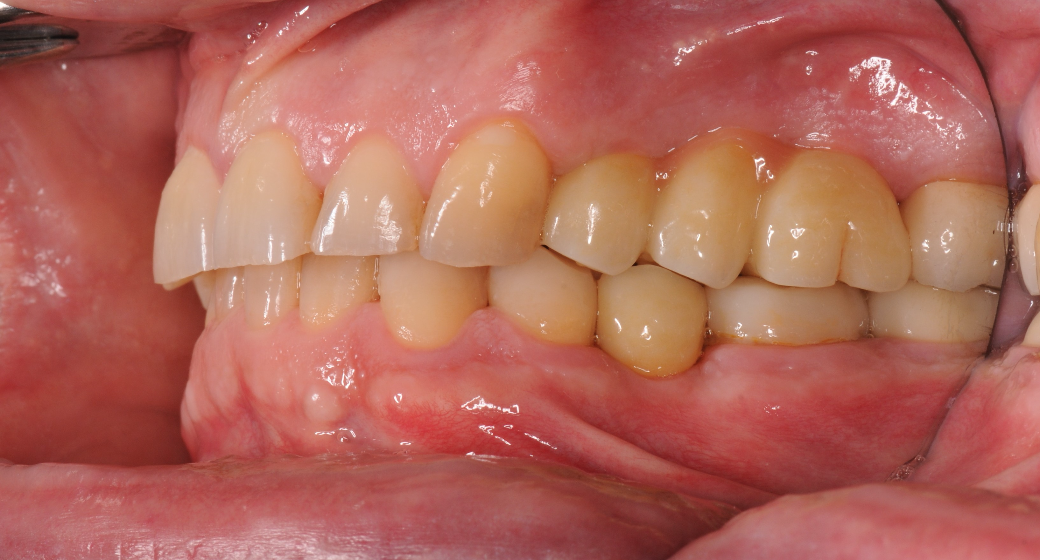

Nachher

Behandlung Vorher-Nachher-Bild | Implantate  | von Dr. med. dent.  Gero  Böthig  | Bernried am Starnberger See d9d4f495 Nachher-Bild

Alle durchgeführten Behandlungen bei diesem Fall: Implantate

24 Z.n. Endo + Krone - 25 Brückenglied - 26 Brückenglied - 27 Krone; 35 fehlt

Entfernung 24 + keramisches Sofortimplantat - 25 Keramikimplantat - 26 Keramikimplantat + interner Sinuslift; 35 Keramikimplantat Alle Implantate wurden mit Zirkonkronen versorgt.

männlich, 56 Jahre